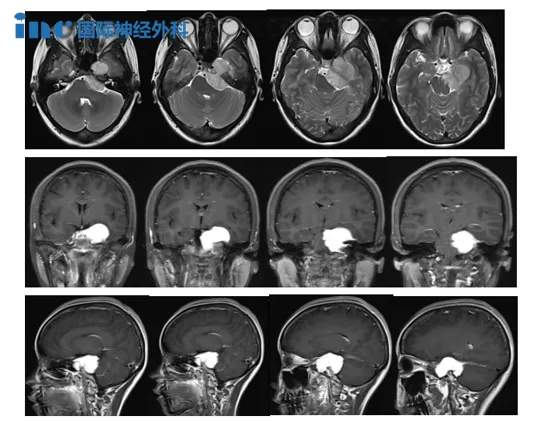

而脑膜瘤患者小宛耐心地等待着这位国际颅底大咖福教授为自己进行的手术。在两月前,她在体检中发现颅内占位性改变。随后,她接受了进一步检查,发现左侧岩尖区团块状占位,考虑脑膜瘤。小宛的主要症状为左眼视力下降,自诉无其余异常,神经功能也未发现异常。考虑到病变的大小与患者的年龄,福教授建议她进行手术,她也及时抓住了福教授此次北京天坛医院手术交流的机会。